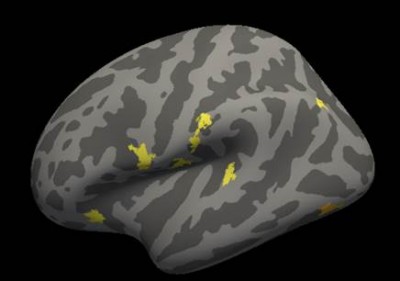

3. Научные исследования структурно-функционального состояния головного мозга при различных неопухолевых и опухолевых заболеваниях.

Для этого применяется методика функциональной МРТ в покое и сложные постпроцессорные алгоритмы построения карт коннективности головного мозга.

Работы ведутся совместно с учеными НИО неврологии и нейрохирургии Центра, а также специалистами других организаций города и страны.

|

|

| Коннектом головного мозга. Мозжечковая рабочая сеть покоя. | Статистическая обработка данных толщины коры головного мозга пациентов при рассеянном склерозе. |